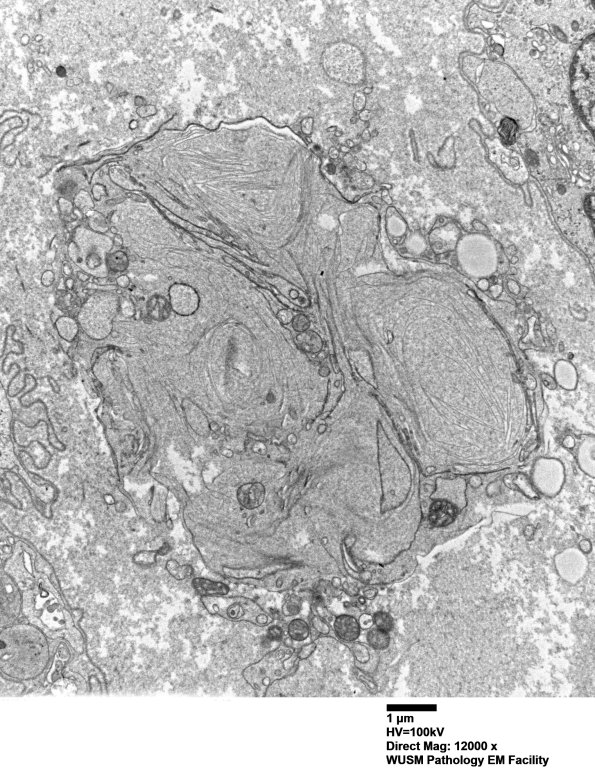

This image shows a large amount of residual axonal and myelin debris within a Schwann cell adjacent to an apparent macrophage process. (Electron micrograph)